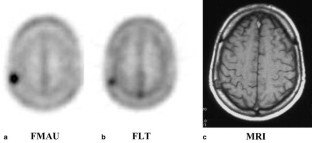

Active tumors in the breast, brain, lung and prostate were clearly visualized with standardized uptake values (SUVs) of 2.19, 1.28, 2.21, and 2.27–4.42, respectively. Unlike with other tracers of proliferation, low uptake of [18F]FMAU was seen in the normal bone marrow (SUVmean 0.7), allowing visualization of metastatic prostate cancer (SUV 3.07). Low background was also observed in the brain, pelvis, and thorax, aside from heart uptake (SUV 3.36–8.78). In the abdomen, increased physiological uptake was seen in the liver (SUV 10.07–20.88) and kidneys (SUV 7.18–15.66) due to metabolism and/or excretion, but the urinary bladder was barely visible (SUVmean 2.03). On average, 95% of the activity in the blood was cleared within 10 min post injection and an average of 70% of the activity in the urine was intact FMAU at 60 min post injection.

Tumors in the brain, prostate, thorax, and bone can be clearly visualized with FMAU. In the upper abdomen, visualization is limited by the physiological uptake by the liver and kidneys.